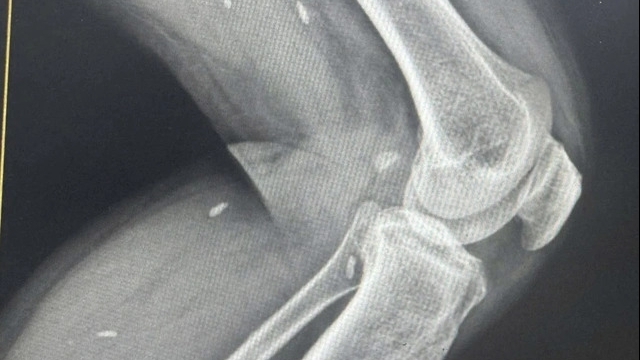

Mới đây, Bệnh viện Hữu nghị Việt Đức tiếp nhận trường hợp người bệnh L.V.H (21 tuổi) đến từ Hòa Bình nhập viện do tai nạn xe máy trong tình trạng đa chấn thương: Chấn thương sọ não, chấn thương hàm mặt, vết thương vùng bẹn trái.

Sau khi tiến hành thăm khám và cho người bệnh thực hiện các xét nghiệm cần thiết, các bác sĩ phát hiện người bệnh có tổn thương tĩnh mạch chậu bên trái, có huyết khối tĩnh mạch chậu ngoài và đùi bên trái, đứt rời hoàn toàn bó mạch thừng tinh bên trái, đứt rời ống dẫn tinh trái, tổn thương tĩnh mạch cầu ngoài bên trái.

Trước tổn thương phức tạp về nam học đứt rời hoàn toàn bó mạch thừng tinh bên trái, đứt rời ống dẫn tinh trái, tổn thương tĩnh mạch cầu ngoài bên trái, các bác sĩ Trung tâm Nam học đã xử lý cắt lọc và nối trực tiếp ống dẫn tinh bằng kĩ thuật vi phẫu 2 lớp. Do mạch tinh kích thước nhỏ 1mm và lòng đường ống dẫn tinh kích thước dưới 1mm nên các bác sĩ đã sử dụng chỉ vi phẫu 9.0 và chỉ vi phẫu 10.0 cùng hệ thống kính vi phẫu phóng đại từ 10 đến 20 lần để có thể quan sát rõ tổn thương và nối lại vết thương đứt rời cho bệnh nhân. Đây là kĩ thuật tiên tiến nhất hiện nay giúp mang lại tỉ lệ thành công cao nhất.

Ca phẫu thuật diễn ra trong 8 tiếng đồng hồ đã kết thúc thành công tốt đẹp. Sau mổ tình trạng người bệnh toàn thân ổn định, bụng mềm, chân trái có thể vận động được, vùng bẹn bìu không bị tím, siêu âm mạch máu cấp máu cho tinh hoàn tốt, không thấy thiếu máu tinh hoàn, siêu âm có đùi không thấy huyết khối tĩnh mạch đùi nông sâu. Hiện bệnh nhân ổn định và đã được xuất viện.